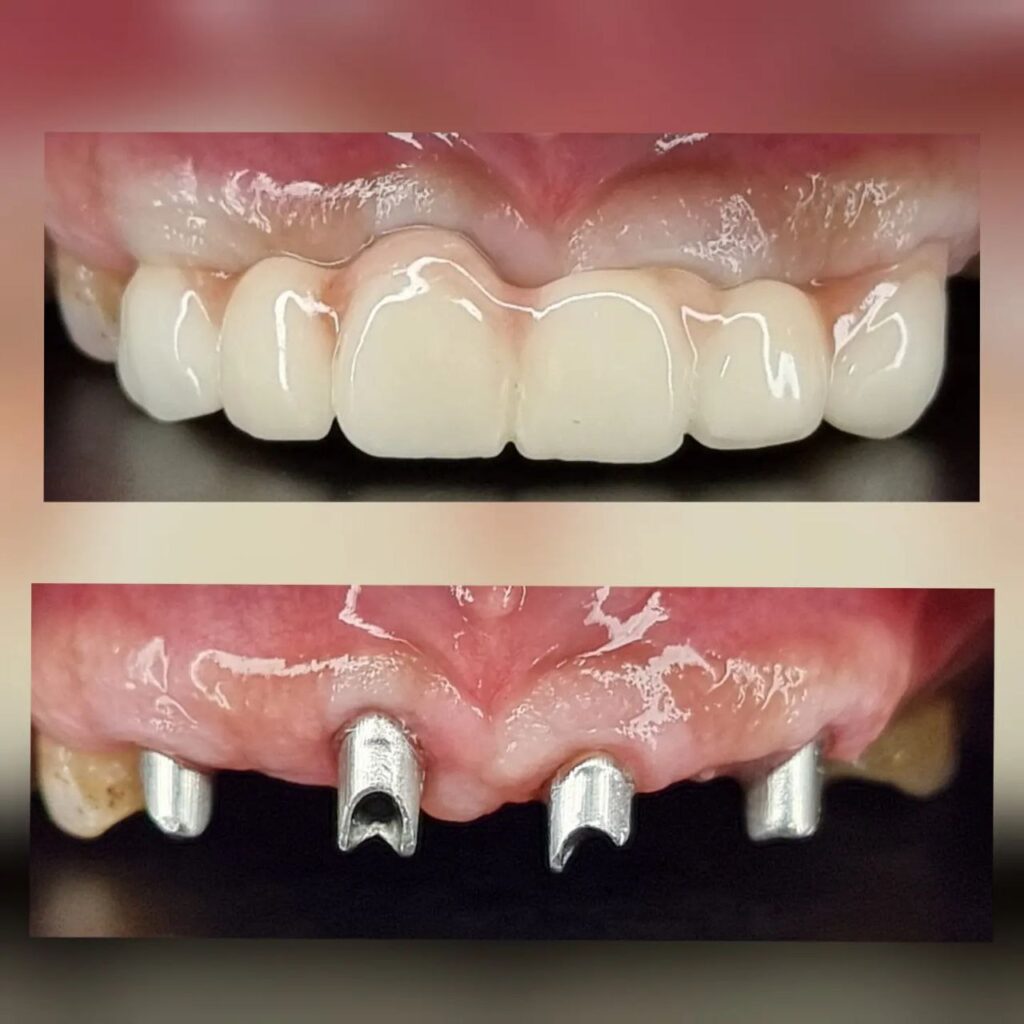

کاشت ایمپلنت دندان

اطمینان حاصل کردن از اینکه دندانهایتان به نحوی زیبا و طبیعی جایگزین شدهاند، از اهمیت بسیاری برخوردار است. ایمپلنت دندان به عنوان یک روش درمانی دائمی در دندانپزشکی شناخته میشود که حاصل آن، یک دندان زیبا و طبیعی در دهان شما خواهد بود.

هرچند که این روش درمانی هزینهی بیشتری نسبت به روشهای دیگر دارد، اما ارزش زیبایی که ایجاد میکند، قابل انکار نیست. ایمپلنتها به قدری شبیه به دندانهای طبیعی هستند که به سختی میتوان آنها را از دیگر دندانها تشخیص داد.